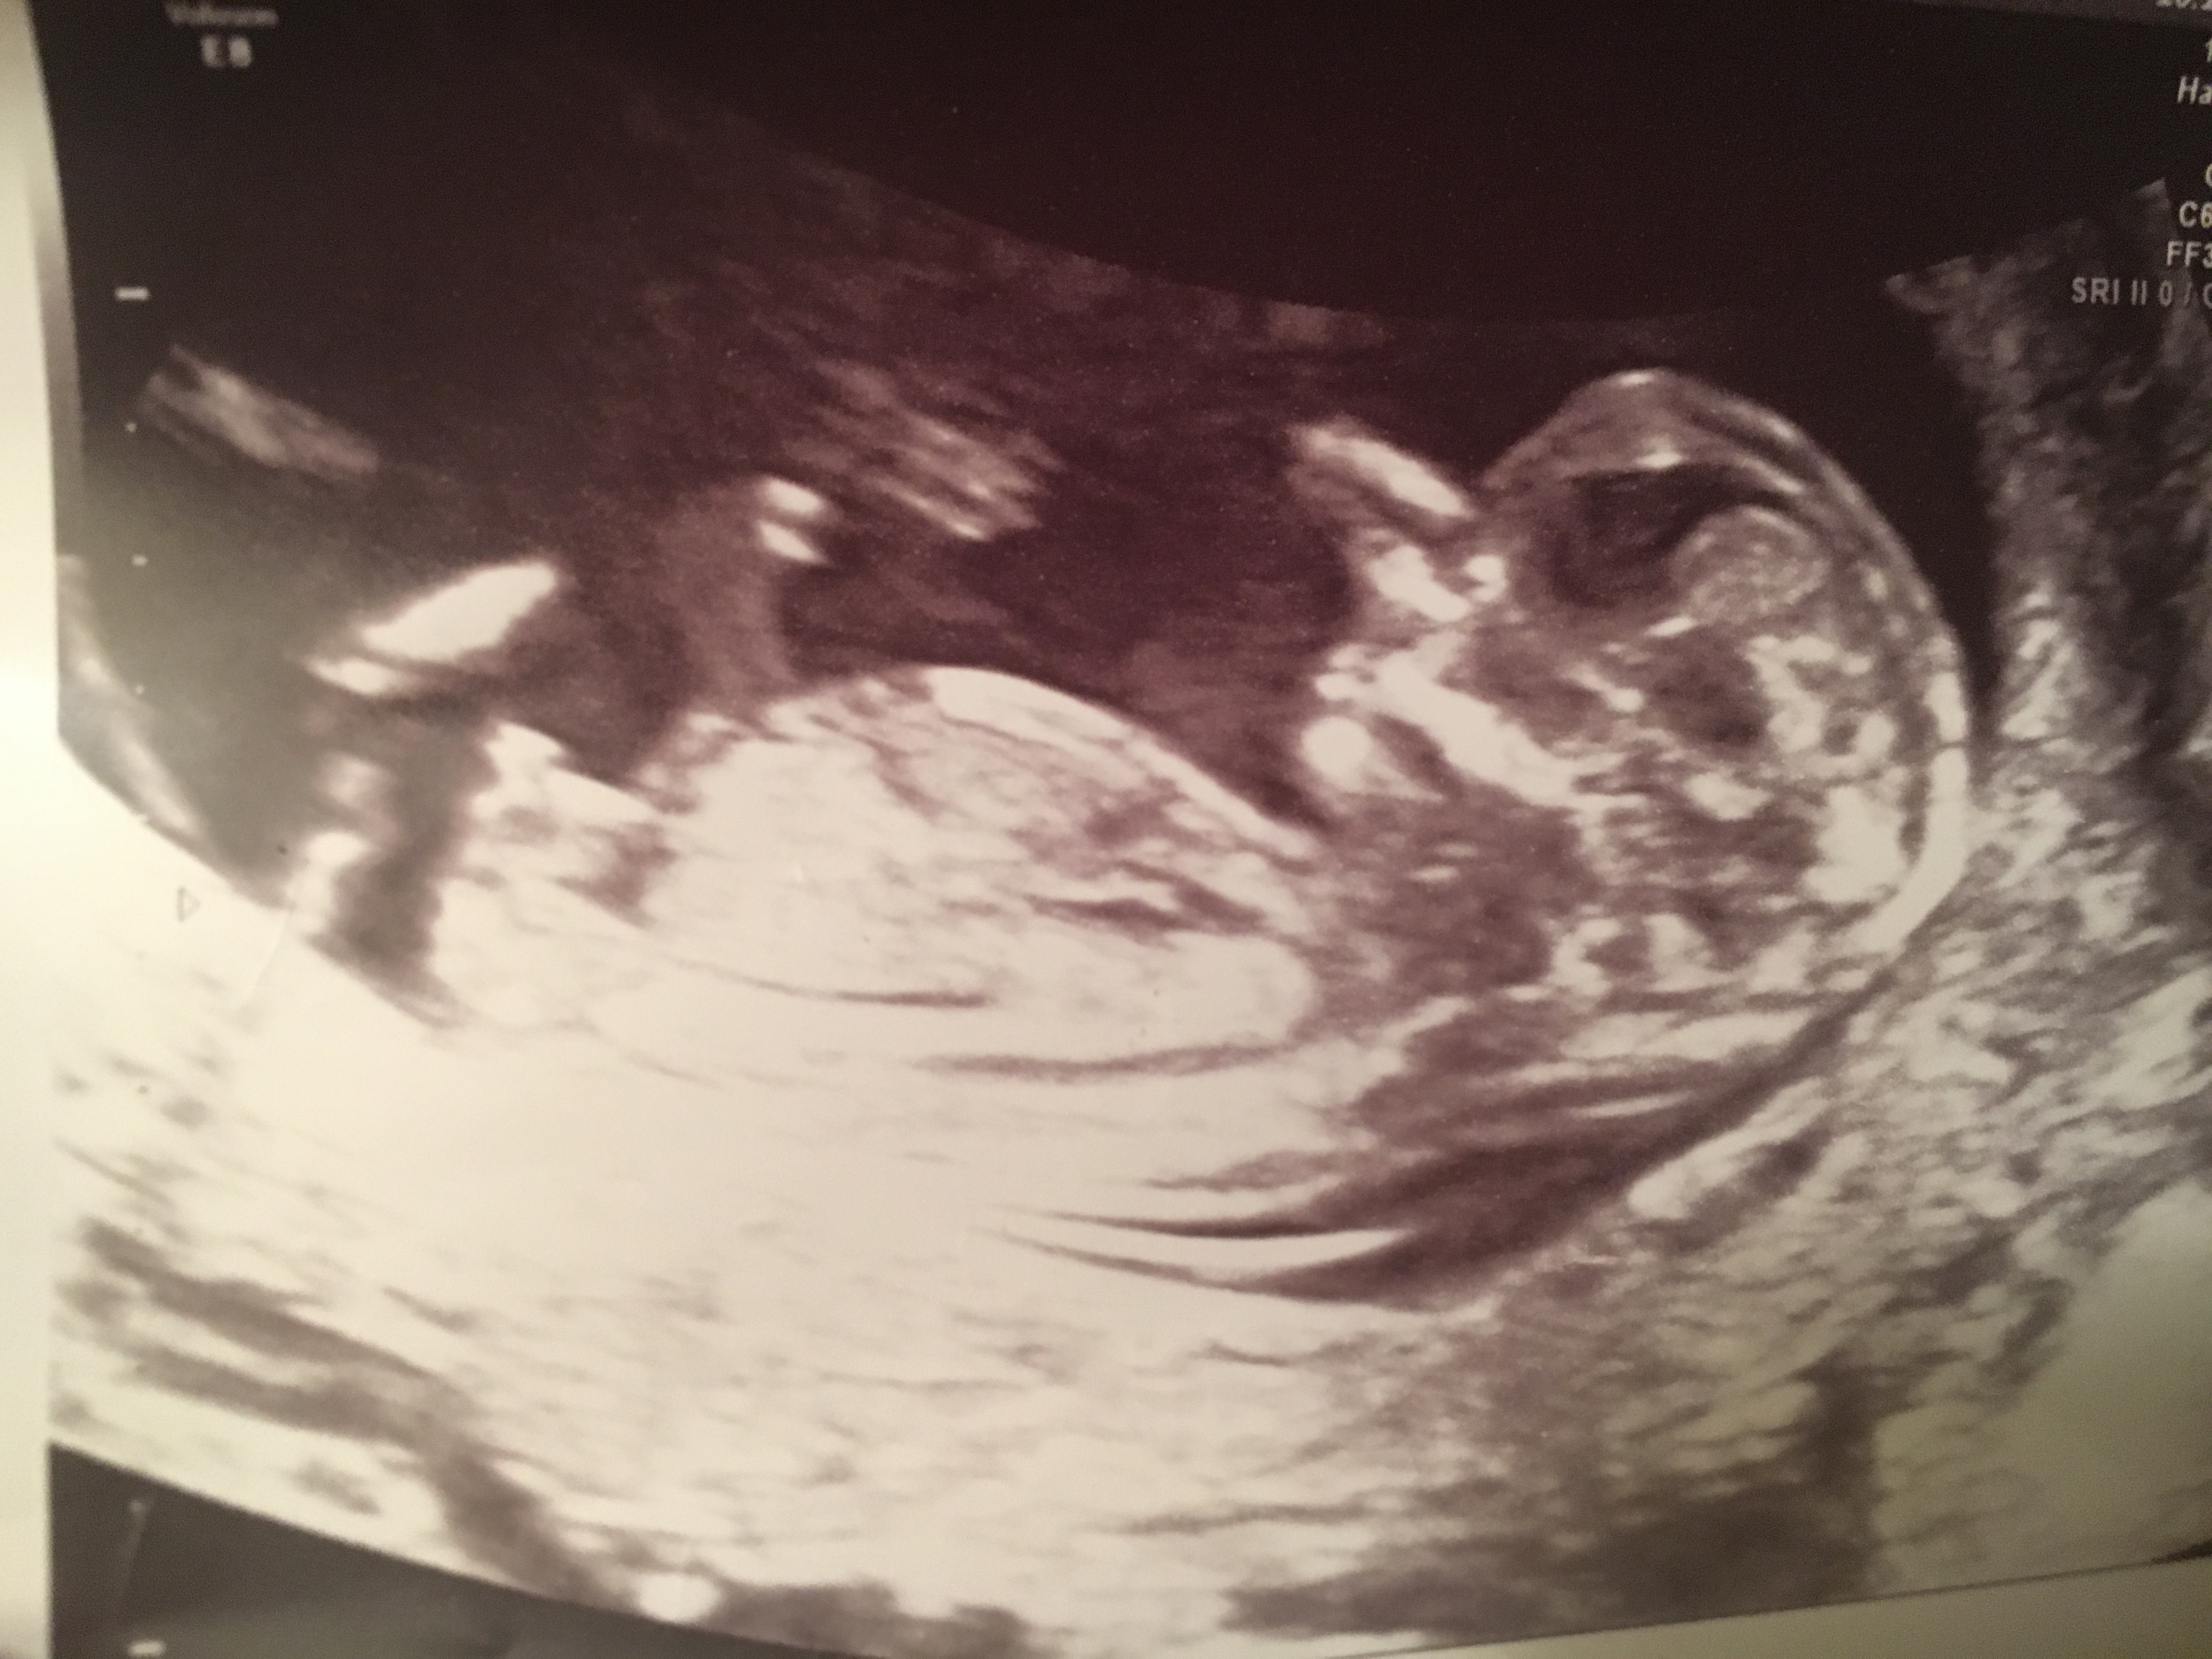

Scan done at 12 weeks 6 days

Looks awfully boy like to me, feeling quite deflated as this is our final baby and will be boy # 5. Should I hold onto any glimmer of hope?? I can’t tell if I’m reading the angle right-doesn’t measure over 30 degreees but I don’t know if the amount even matters or just the fact that it’s going up.